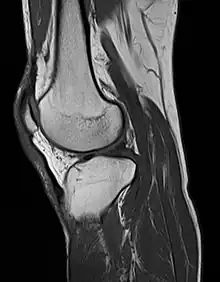

MRI of the knee

MRI uses strong magnetic fields to align atomic nuclei (usually hydrogen protons) within body tissues, then uses a radio signal to disturb the axis of rotation of these nuclei and observes the radio frequency signal generated as the nuclei return to their baseline states.[10] The radio signals are collected by small antennae, called coils, placed near the area of interest. An advantage of MRI is its ability to produce images in axial, coronal, sagittal and multiple oblique planes with equal ease. MRI scans give the best soft tissue contrast of all the imaging modalities. With advances in scanning speed and spatial resolution, and improvements in computer 3D algorithms and hardware, MRI has become an important tool in musculoskeletal radiology and neuroradiology.

One disadvantage is the patient has to hold still for long periods of time in a noisy, cramped space while the imaging is performed. Claustrophobia (fear of closed spaces) severe enough to terminate the MRI exam is reported in up to 5% of patients. Recent improvements in magnet design including stronger magnetic fields (3 teslas), shortening exam times, wider, shorter magnet bores and more open magnet designs, have brought some relief for claustrophobic patients. However, for magnets with equivalent field strengths, there is often a trade-off between image quality and open design. MRI has great benefit in imaging the brain, spine, and musculoskeletal system. The use of MRI is currently contraindicated for patients with pacemakers, cochlear implants, some indwelling medication pumps, certain types of cerebral aneurysm clips, metal fragments in the eyes, some metallic hardware due to the powerful magnetic fields, and strong fluctuating radio signals to which the body is exposed. Areas of potential advancement include functional imaging, cardiovascular MRI, and MRI-guided therapy.